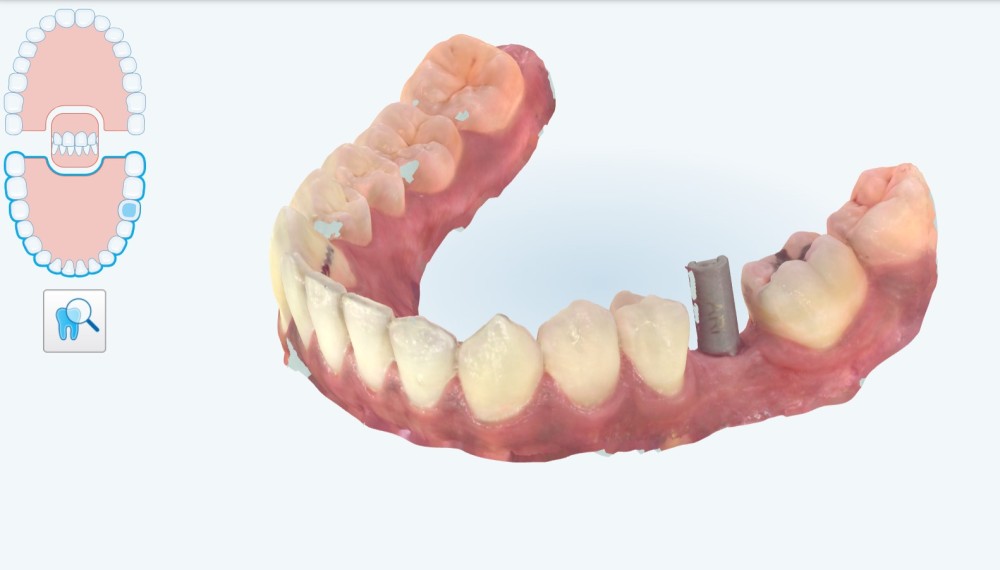

Pour cela nous décidons de poser notre implant de façon « Full guidé », c’est-à-dire planifié en amont dans une position alliant un placement optimal osseux et prothétique. Nous aurons besoin d’une empreinte numérique qui va nous fournir un fichier STL (fig. 1) , ainsi que les information sur l’os fournies par le cone-beam (CBCT) . Nous décidons à ce stade de faire modéliser le guide par une plateforme de conception (design4me) qui s’occupera du matching de nos DATA. Après validation de la planification nous recevons notre fichier (fig. 2) prêt à être imprimé localement grâce à une imprimante 3D (Nextdent).

3 mois après cicatrisation , nous reprenons notre camera en main, et cette fois ci, nous allons prendre l’empreinte de notre « scanbody » qui est le transfert d’empreinte numérique (fig. 4) correspondant à notre implant (Megagen). C’est la que la magie opère… Fini les portes empreintes individuels, à perforer etc. On place le scanbody et on prends l’empreinte (haut , bas , occlusion). On peut même prendre le profil d’émergence sur un scan supplémentaire en quelques secondes.